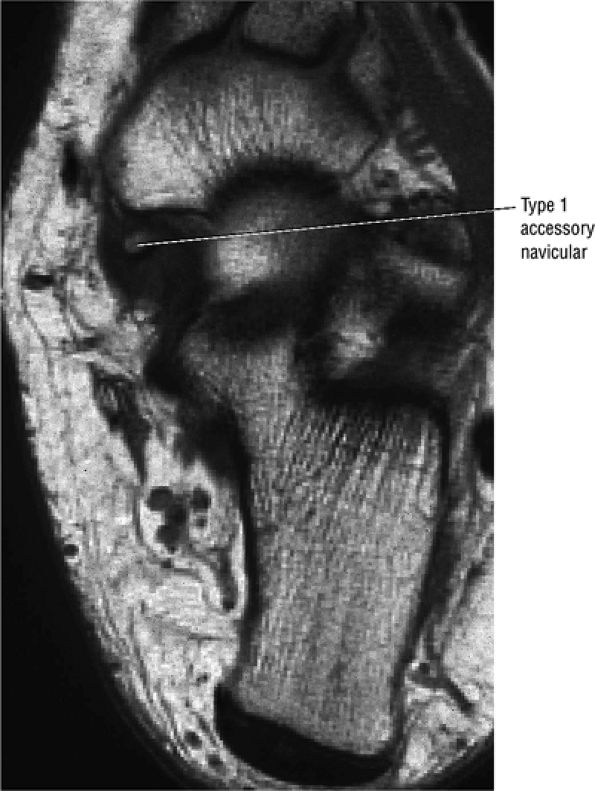

hyperintensity on T1-weighted images, secondary to fatty marrow. This finding should not be mistaken for tendon degeneration or a tear. Accessory bones, including the os tibiale externum (an accessory navicular bone medial to the navicular) and the os trigonum (located posterior to the talus and occurring approximately 10% of the time), represent commonly seen secondary ossification centers. These are normal variants that may be misinterpreted as a fracture or loose body.21